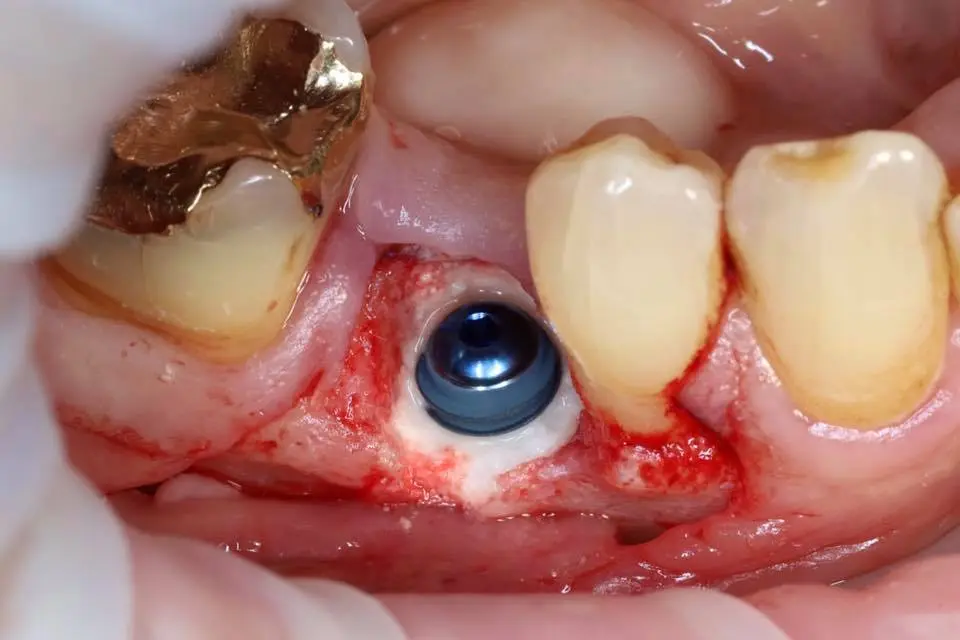

Seminaariesitykset keskittyvät täysin synteettiseen EthOss-biomateriaaliin, joka on kehitetty edistämään potilaan omaa luun uudistumista hammasimplanttien ja suukirurgian yhteydessä. EthOss koostuu β-trikalsiumfosfaatista ja kalsiumsulfaatista, jotka luovat ihanteelliset olosuhteet luun kasvulle ilman sulamattomia vieraspartikkeleita tai eläinperäisiä aineita, korvautuen kokonaan elävällä isäntäluulla noin 6–12 kuukaudessa.

Esityksissä käsitellään materiaalin valmistelua, käyttöä luusiirteissä sekä kliinisiä tuloksia, kuten nopeaa luunmuodostusta (jopa 50 % uutta luuta 12 viikossa), ilman tarvetta erilliselle kollageenikalvolle.

This lecture will explore how surgical simplicity combined with biologically active materials can achieve outstanding results across a range of indications — from socket preservation and regeneration to sinus lifting. Through clinical cases and practical protocols, Dr. Stuart Kilner will demonstrate how to optimise handling, improve efficiency, and achieve stable regeneration by working with, not against, the body’s innate capacity to heal.

EthOss cases by Dr Stuart Kilner